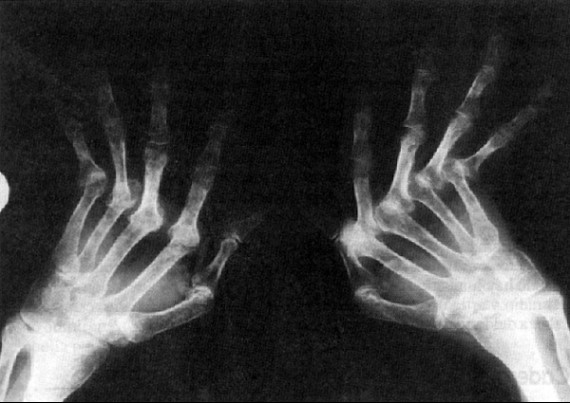

3. Artritris Reumatoide

En México, un millón 700 mil personas, de entre 20 y 50 años padecen artritis reumatoide, lo que representa un grave problema de salud pública porque es un mal discapacitante y caro, al alcanzar costos anuales por más de 600 dólares por paciente.

El reumatólogo Conrado García García, adscrito al Hospital General de México, informó en rueda de prensa que en el país 1.6 por ciento de los 112 millones de la población general sufre artritis, según la estadística actualizada sobre esa enfermedad.

La Asociación Mexicana de Familiares y Pacientes con Artritis Reumatoide (Amepar), explica que este padecimiento ataca a más mujeres que a hombres en una relación que va de tres a uno y contrario a lo que se piensa, afecta a la población de adultos jóvenes entre 20 a 50 años, que es la edad productiva, por lo que representa un grave problema de discapacidad laboral y un fuerte cargo económico para las familias y los pacientes.

En este contexto, Amepar informó que en México no se cumple con la recomendación de la OMS de que haya un reumatólogo por cada cien mil habitantes, pues sólo se tiene el registro de unos 560 certificados, esto es un especialista por cada 200 mil habitantes, lo que no es suficiente.

La enfermedad no tiene cura, pero es tratable. En la mayoría de los casos el diagnóstico es tardio y por tanto el problema es mayor. El paciente puede presentar síntomas como dolor en las articulaciones de rodillas, manos, codos, pies o tobillos que persistan por más de seis semanas.